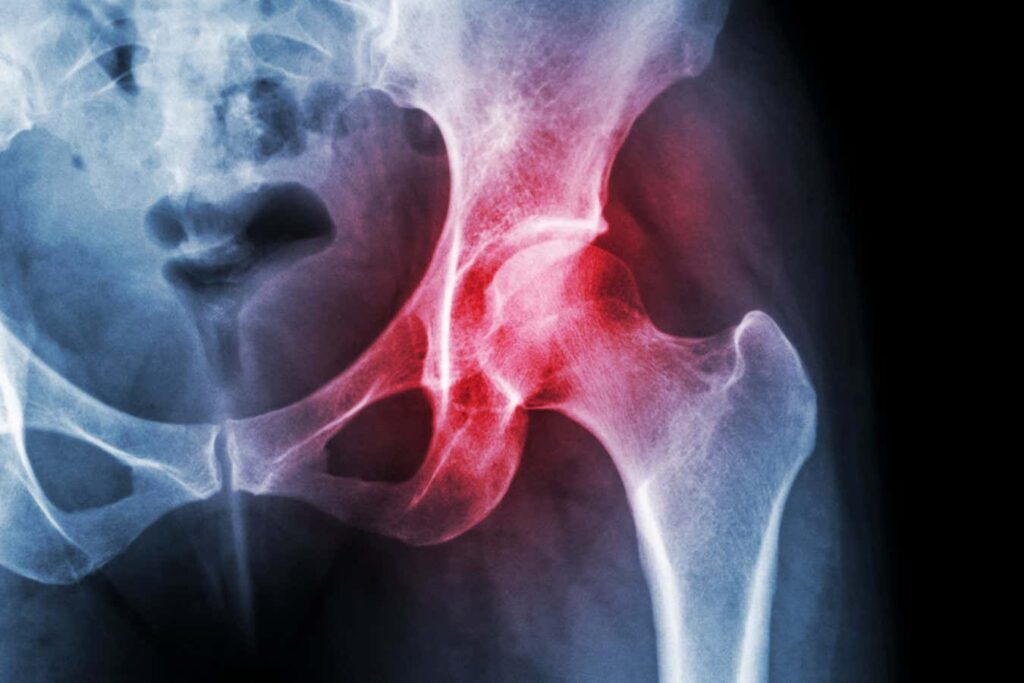

Osteoarthritis affects 530 million people worldwide

Osteoarthritis is the most common form of arthritis and is approximately 530 million people worldwide. It occurs when the cartilage that cushions bones breaks down, causing joint stiffness and pain. Treatment options for this condition are limited, and there is no treatment to prevent cartilage degeneration.